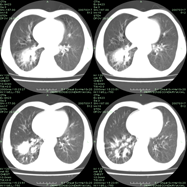

以下是引用qian在2007-4-23 19:06:00的发言:[br]胰腺体积增大,轮廓欠规则,肝轮廓波浪状改变,肝裂增宽,肝周、脾周有液性密度,腹膜后肿大淋巴结,考虑1、胰腺癌伴腹膜后淋巴结转移;2、肝硬化伴腹水。

以下是引用卜一在2007-4-23 20:12:00的发言:[br]胰腺体积增大,轮廓欠规则,肝轮廓波浪状改变,肝裂增宽,肝周、脾周有液性密度,腹膜后肿大淋巴结,考虑1、胰腺癌伴腹膜后淋巴结转移;2、肝硬化伴腹水。支持!